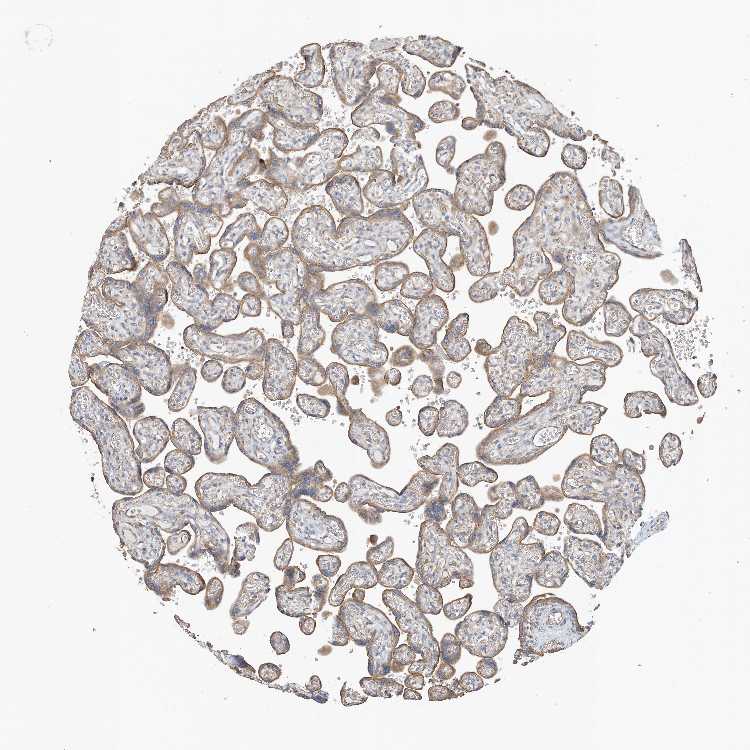

TCP10L2